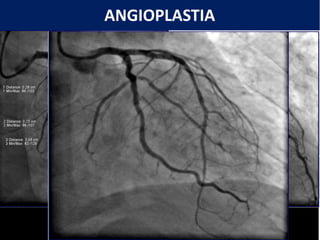

O documento descreve procedimentos de hemodinâmica como angioplastia e angiografia coronariana. Explica que a hemodinâmica estuda o movimento do sangue e é usada para diagnóstico e tratamento. Detalha a angiografia coronariana, que visualiza as artérias do coração, e a angioplastia, que trata obstruções com balões e stents.